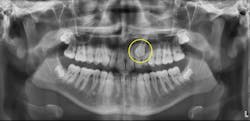

Look at the size of the follicle around the unerupted canine. Canines that are having problems with eruption tend to have larger than normal follicles, as seen in Figure 2.